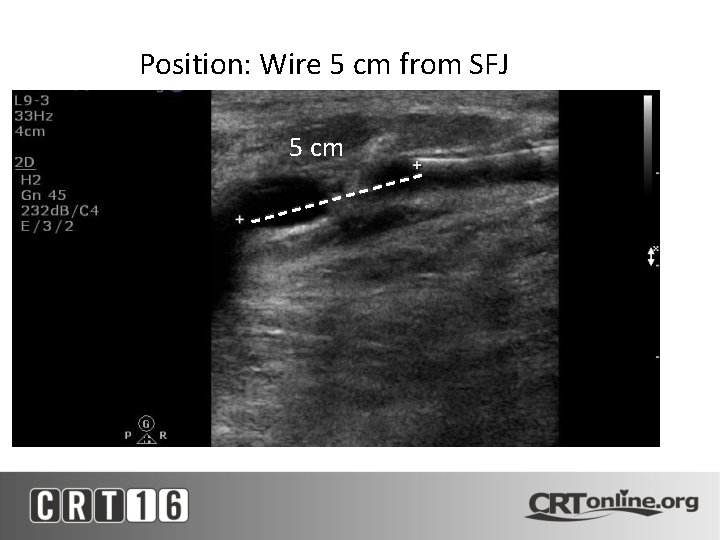

Position: Wire 5 cm from SFJ 5 cm

Wire Agitation with STS Infusion